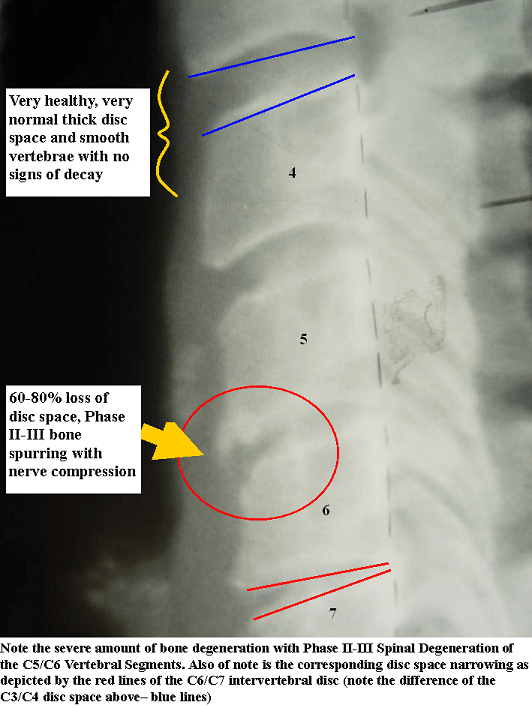

Xray of the lumbar spine (lateral view) showing the anterior spurs in

Xray of the lumbar spine (lateral view) showing the anterior spurs in What Is A Spur In The Spine Bone spurs (also called osteophytes) are smooth, hard bumps of extra bone that form on the ends of bones. Bone spurs can grow into the spinal canal, where the spinal cord travels, leaving less space for the spinal cord. If bone spurs occur in the spine, they can cause pain and loss of motion, but they can also pinch the. What Is A Spur In The Spine.